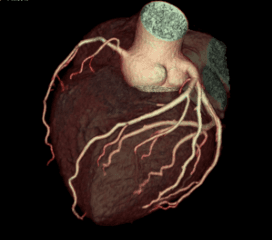

Cardiac Scan 1

Cardiac Scan 2

Cardiac Scan 3

Cardiac Scan 4

Cardiac Scan 5

Cardiac Scan 6

Cardiac Scan 7

Cardiac Scan 8

Cardiac Scan 9

Cardiac Scan 10

Cardiac Scan 11

Cardiac Scan 12

Coronary Angiogram

A CT Coronary Angiogram is a non-invasive imaging test that uses a CT scanner, and contrast dye to create detailed 3D pictures of your heart's arteries, revealing plaque, blockages, or narrowing (stenosis) that can cause heart problems like chest pain.